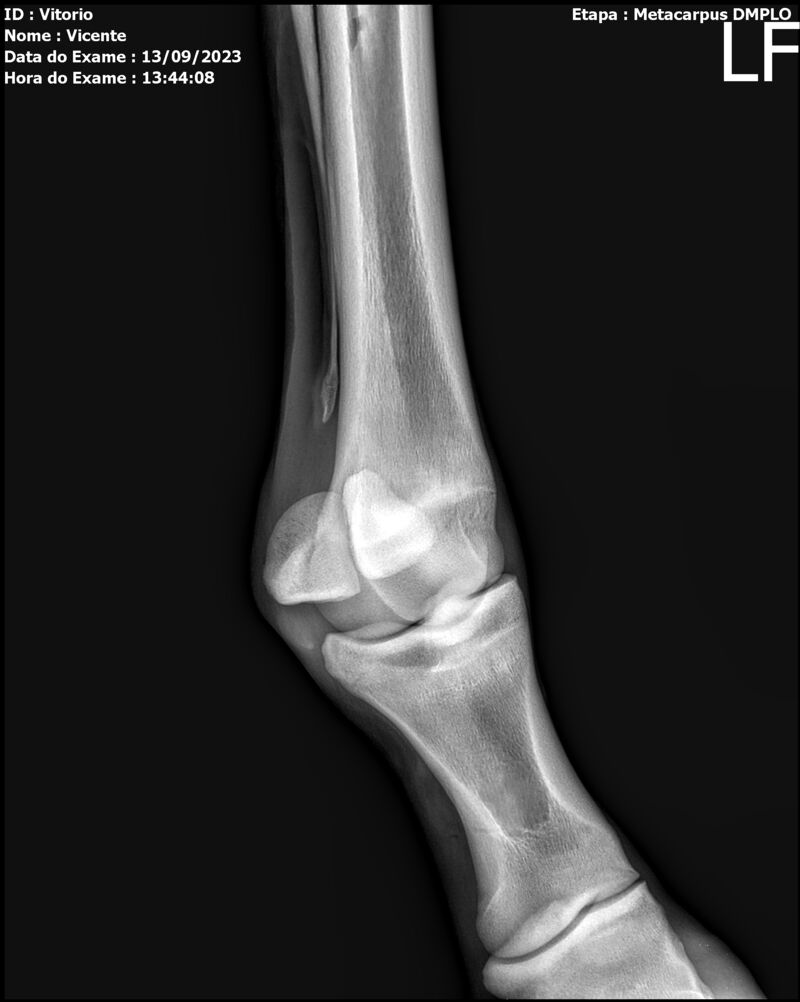

LOTE 13

THUNDER ZC

Raça: BRASILEIRO DE HIPISMO

Sexo: MACHO - POTRO

Nascimento: 17/09/2022

Altura Aproximada: 1,54

Pel.: CASTANHO

Registro: EM AND

Vend.: VICENTE CONTE

Local : PORTO FELIZ/SP